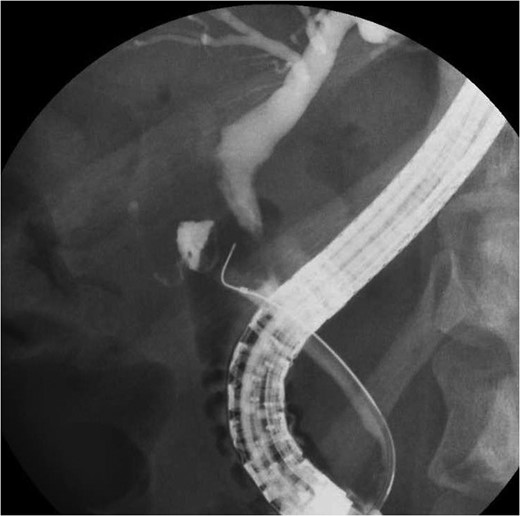

A 36-year-old woman was admitted to our hospital due to appetite loss, nausea, and back pain. A physical examination disclosed right hypochondriac tenderness and obvious jaundice. Laboratory studies showed elevated levels of total bilirubin (9.7 mg/dl), direct reacting bilirubin (6.0 mg/dl), aminotransferase (AST 281 U/l, ALT 362 U/l), alkaline phosphatase (1945 U/l,) and γ-glutamyltransferase (1769 U/l); however, her white blood cell count and C-reactive protein level were within the normal ranges. Magnetic resonance cholangiography revealed that the intrahepatic and common hepatic bile ducts were dilated, and that the gallbladder was distended (Fig. 1). Endoscopic retrograde cholangiography demonstrated a round-shaped filling defect at the confluence of the bile duct (Fig. 2). Based on the findings, the patient was diagnosed with Mirizzi syndrome Type II according to the Csendes classification [1]. Although, the endoscopic removal of the impacted gallstone was unsuccessful, a stent tube was placed for endoscopic retrograde biliary drainage in order to improve the patient’s obstructive jaundice. We planned to perform laparoscopic surgery.

Endoscopic retrograde cholangiography demonstrated a filling defect at the confluence of the bile duct.